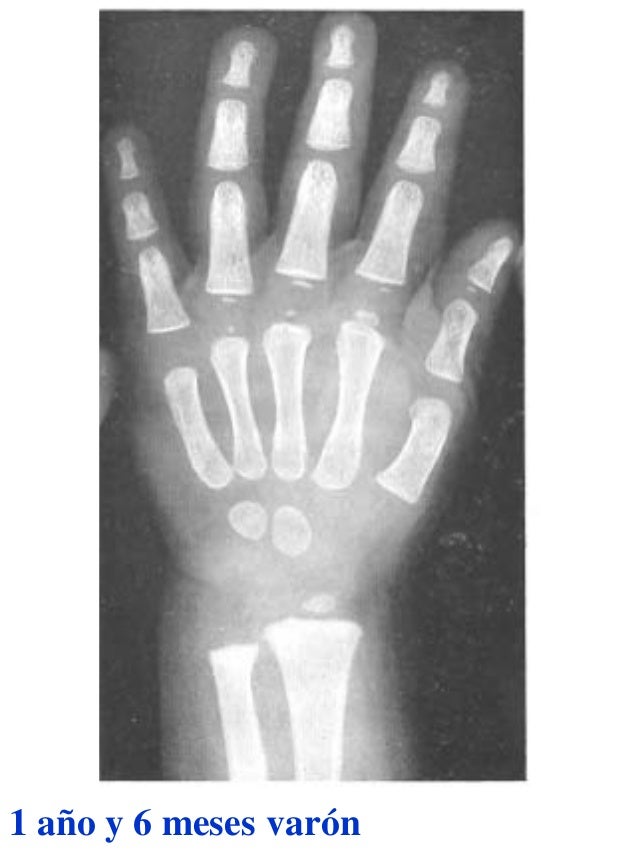

Tablas De Greulich Y Pyle The standards established by greulich and pyle, undoubtedly the most popular method, consist of two series of standard plates. The standards established by greulich and pyle, undoubtedly the most popular method, consist of two series of standard plates. El documento lista las edades. This systematic review summarizes the. The greulich and pyle method is one of the two main ways to assess the bone age of children. Both main methods of bone age. Scribd is the world's largest social reading and publishing site. 153 recomendaciones • 616,869 vistas. Atlas greulich y pyle | pdf | descarga gratuita. The greulich and pyle atlas is used to estimate the age of children and adolescents. The radiographic atlas of skeletal development of the hand and wrist by ww greulich and si pyle is a classic radiological.

Tablas De Greulich Y Pyle . Scribd is the world's largest social reading and publishing site. This systematic review summarizes the. The radiographic atlas of skeletal development of the hand and wrist by ww greulich and si pyle is a classic radiological. The standards established by greulich and pyle, undoubtedly the most popular method, consist of two series of standard plates. The greulich and pyle method is one of the two main ways to assess the bone age of children. El documento lista las edades. Both main methods of bone age. 153 recomendaciones • 616,869 vistas. Atlas greulich y pyle | pdf | descarga gratuita. The greulich and pyle atlas is used to estimate the age of children and adolescents.